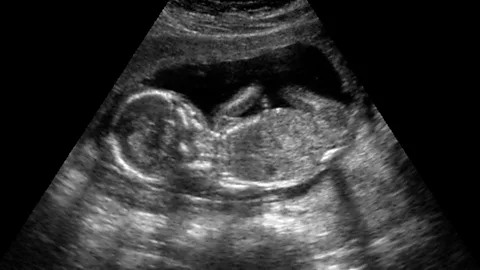

Where it gets particularly sticky is if the victim is pregnant. In these cases, the patient’s family have a heart-breaking choice to make. They can either accept that they’ve lost her unborn baby, or begin the intensive and often gruesome battle to keep her going long enough to deliver, which is usually when the foetus is about 24-weeks-old.

Back in 2013, Marlise Munoz was found unconscious at her home in Texas. Her doctors suspected that she had suffered a pulmonary embolism and discovered that she was 14 weeks pregnant. Two days later she was declared dead. Munoz was a paramedic and had previously told her husband that in case of brain death, she would not want to be kept alive artificially. He petitioned to have her life support removed – but the hospital refused.

The circumstances are extremely rare, with only about 30 reported cases between 1982 and 2010, but the tug-of-war between the interests of the mother and those of her unborn baby begs the question: which human rights should we retain when we’re dead?